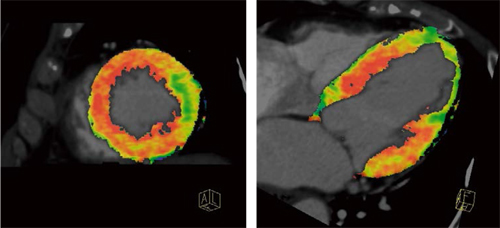

経時的に撮影を行うダイナミックスキャンにおいても,専用の被ばく低減アプリケーションである“4D Noise Reduction”(時間軸データにおけるノイズリダクション法)を搭載して被ばく低減に努めており,30秒間のダイナミックデータを7mSv程度の被ばくで取得可能である(図3)。

図3 Heart Perfusion(心電図同期シャトルスキャンモード)を用いた

ダイナミック負荷心筋パフュージョン解析結果

PSARと4D Noise Reductionを用いることで,被ばく低減も考慮しながら,より精度の高い心筋血流評価を行う。